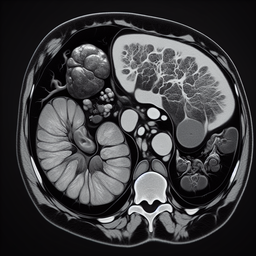

МРТ селезінки

МРТ селезінки – це високоточний метод візуалізації, який використовують для діагностики різних захворювань цього органу. За допомогою магнітно-резонансної томографії лікарі можуть отримати детальні зображення селезінки без застосування рентгенівських променів.

Це дослідження особливо корисне для виявлення:

1. Вроджених аномалій.

2. Травм або розривів селезінки.

3. Запальних процесів.

4. Доброякісних та злоякісних пухлин.

5. Збільшення селезінки (спленомегалії).

Процедура є безболісною і безпечною, але може тривати більше часу, ніж інші методи візуалізації. Зазвичай не потребує спеціальної підготовки, хоча іноді може знадобитися використання контрастних речовин для кращої видимості.